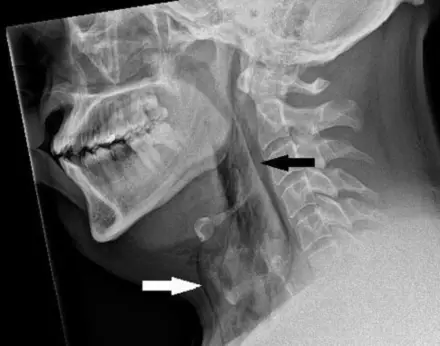

In this month's British Medical Journal (BMJ) report, titled 'Spontaneous tracheal perforation following a sneeze', they explained: "A man in his 30s, with a background of allergic rhinitis, experienced severe neck pain immediately after an episode of sneezing when he stifled the sneezes by pinching his nose and closing his mouth. This took place while he was driving a car with a seat belt on.

"On examination, his neck was swollen bilaterally, with mild crepitus on palpation and a reduced range of movement of the neck."